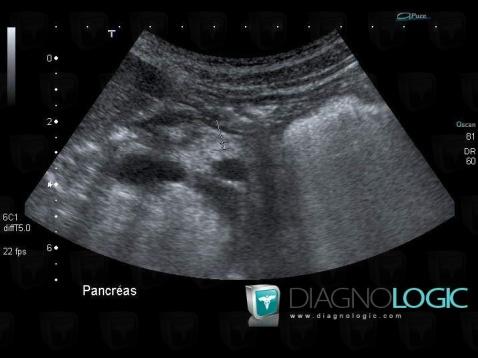

The images below illustrate this case for diagnoses Cystic fibrosis, for the modalities (US)

Here is the specific information in the key image above: - Diagnosis Cystic fibrosis, Location(s) Pancreas, with gamuts Cystic pancreatic lesion